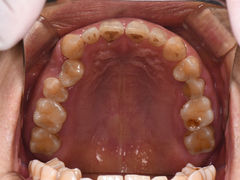

• 固瑞齿科(国贸门诊店)

• -固瑞齿科(国贸门诊店)